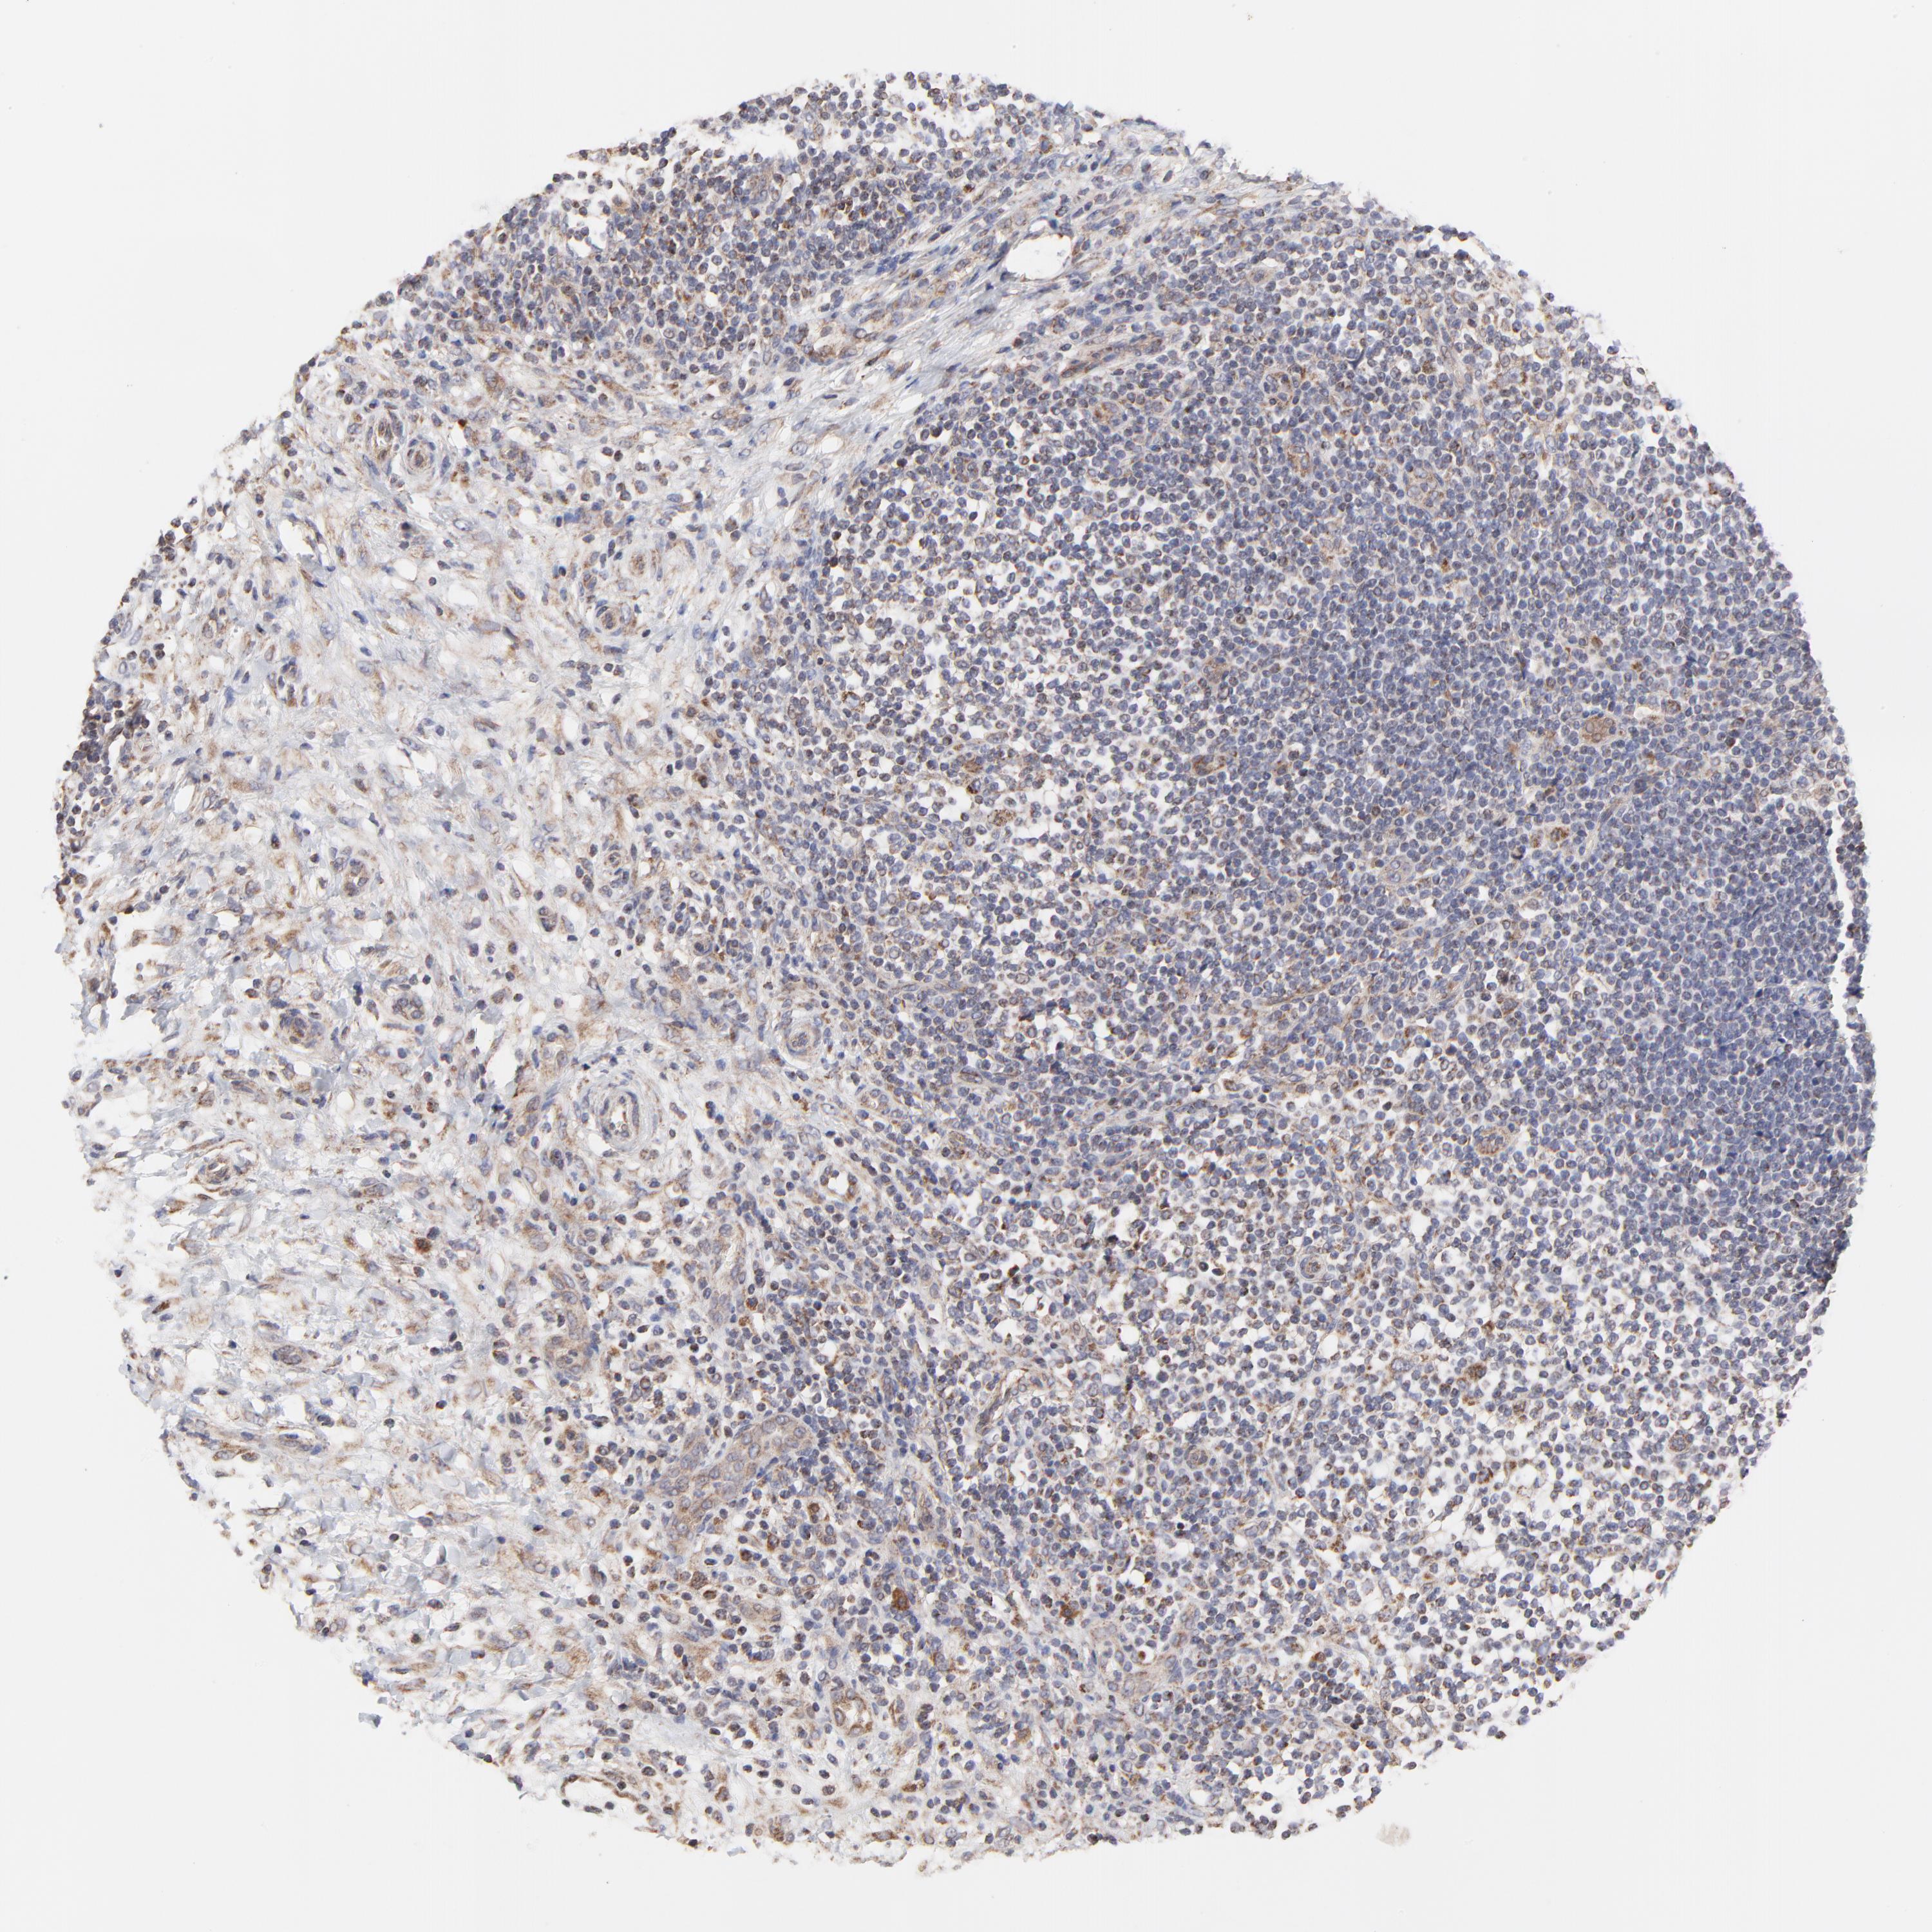

LYMPHOMA - Protein expressioni

A mouse-over function shows sample information and annotation data. Click on an image to view it in a full screen mode. Samples can be filtered based on level of antibody staining by selecting one or several of the following categories: high, medium, low and not detected. The assay and annotation is described here.

Antibody stainingi

Antibody staining in the annotated cell types in the current human tissue is reported as not detected, low, medium, or high, based on conventional immunohistochemistry profiling in selected tissues. This score is based on the combination of the staining intensity and fraction of stained cells.

Each image is clickable and will lead to virtual microscopy that enables deeper exploration of all samples and also displays staining intensity scores, fraction scores and subcellular localization as well as patient and tissue information for each sample.

Antibody HPA003251

Staining

High

Medium

Low

Not detected

Intensity

Strong

Moderate

Weak

Negative

Quantity

>75%

75%-25%

<25%

None

Location

Nuclear

Cytoplasmic/membranous

Cytoplasmic/membranous,nuclear

Malignant lymphoma, non-Hodgkin's type, High grade

Malignant lymphoma, non-Hodgkin's type, Low grade

Hodgkin's disease, NOS